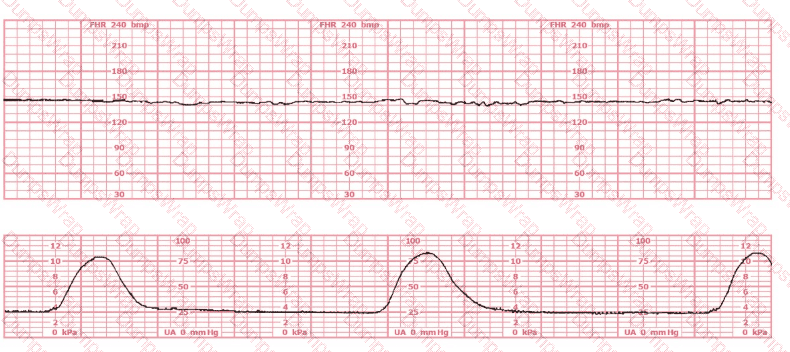

This tracing reflects

Options:

Minimal variability

Moderate variability

Sinusoidal pattern

Answer:

BExplanation:

Comprehensive and Detailed Explanation From Exact Extract (NCC-Recommended Sources Only)

The fetal heart rate (FHR) tracing shown demonstrates a baseline approximately 135–145 bpm with fluctuations of 6–25 bpm, a hallmark of moderate variability. Moderate variability is defined in all NCC-endorsed resources as the normal amplitude range of 6–25 bpm around the fetal baseline.

According to the AWHONN Fetal Heart Monitoring Principles & Practices (2022–2024), moderate variability is considered the single most reliable indicator of adequate fetal oxygenation and intact neurologic pathways, specifically reflecting well-functioning sympathetic and parasympathetic interplay.

The NICHD/NCC standardized definitions included in the NCC C-EFM Candidate Guide state:

Minimal variability: amplitude range ≤ 5 bpm

Moderate variability: amplitude range 6–25 bpm

Marked variability: amplitude > 25 bpm

Sinusoidal pattern: smooth, undulating waveform, 3–5 cycles per minute, equal amplitude, absent beat-to-beat variability

The tracing provided does not show the repetitive, smooth, wave-like pattern of a sinusoidal rhythm; nor does it show flattening associated with minimal variability. Instead, it includes continuous beat-to-beat fluctuation within the moderate range, without periods of absent or minimal variability.

Menihan’s Electronic Fetal Monitoring (5th ed.) and Simpson & Creehan’s Perinatal Nursing (5th ed.) both emphasize that moderate variability is:

A reassuring feature

Indicative of adequate fetal CNS oxygenation

Expected in a reactive, well-oxygenated fetus

A key criterion for Category I classification

Additionally, Miller’s EFM Pocket Guide reiterates that variability between 6–25 bpm is considered the normal (moderate) fetal autonomic response and is not a sinusoidal pattern, which has a fixed amplitude and frequency.

Therefore, based on NCC-standard definitions and the observed amplitude, the correct interpretation is moderate variability.